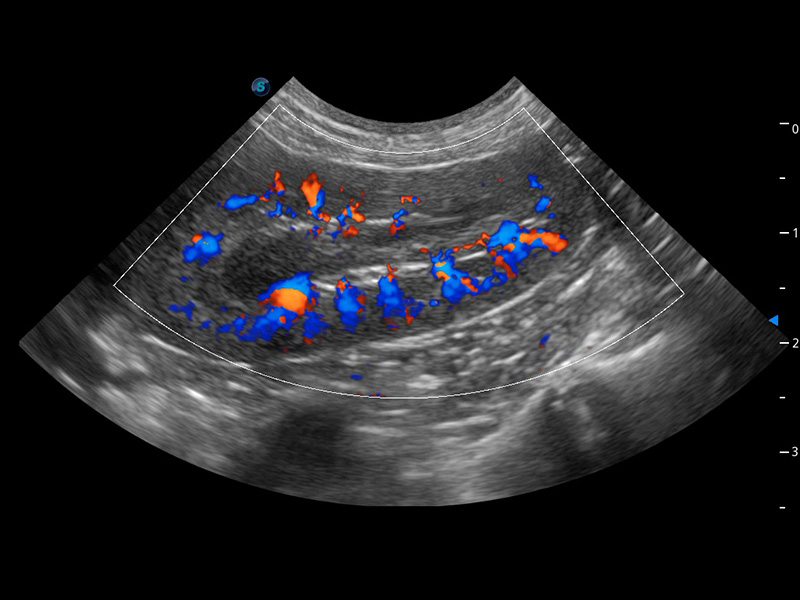

4T血流成像 微察秋毫

融合不同血流成像技术的优势,即可以提升血流成束性,同时可提高血流的视觉敏感性。

PDI 能量多普勒血流

提供高灵敏度和空间分辦率的血流图像,获得更加真实和丰富的诊断信息。

SR Flow 高分辨率血流成像

能够清晰显示细小、低速血流图像,获取传统彩色多普勒技术难以得到的细节和信息。

Micro F 显微血流成像

通过创新的Matrix E自适应滤波器和超长时间域算法,极大提升超低速微细血流的检出能力,同时更精准地滤除软组织和噪声信号,为兽用医生提供以往无法通过常规血流获得的疾病诊断信息。

Bright Flow 立体血流成像

在传统二维血流成像的基础上,呈现血流的立体感,具有动感的生命力之美。精确区分不同血管的空间关系,提高了血流的视觉敏感性。

(犬)四腔心血流

(犬)肾脏血流